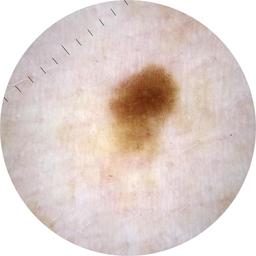

MEL-SELF - Dermoscopic

- Name: MEL-SELF - Dermoscopic

Description:

Dermoscopic lesion images (close-up views of benign and malignant lesions) from the MEL-SELF trial (the Melanoma Self Surveillance trial).